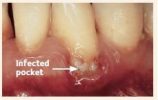

The following images show the progression of gum disease:

2. Infection due to plaque (germs) and calculus (tartar) beginning to destroy the supporting gums and bone around the teeth.